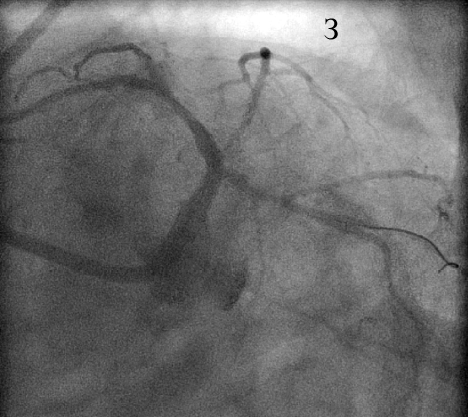

В устье ОВ с переходом на ее проксимальный сегмент был имплантирован стент XienceV (и), после чего выполнена постдилатация по методике «целующихся» баллонов (к). При контрольной КГ стентированные сегменты проходимы, достигнут хороший ангиографический результат (л).